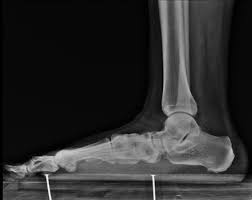

If severe and there is suspicion of major tendon or soft tissue damage an MRI may be performed. Currently Veterans can receive a rating between 0 and 50 percent for pes planus. Through the rating criteria in this code the VA will evaluate your symptoms and give you a rating on a scale of 0 mild disability to 50 pronounced disability. Relationship Between Flat Feet Pes Planus and Veterans.

The VA awards disability compensation for injuries to the Foot and Lower Leg Muscles that are service-connectedThe DoD will also rate service-connected muscle injuries as long as they also make the service member Unfit for DutyFor Reservists the injury must have occurred in the Line of Duty to qualify. The VA rates flat feet as per the 38 CFR 471a Schedule of Ratings Musculoskeletal System with the diagnostic code 5276. Cant find in the cfr the criteria for rating flat feet percentages. Moderate flat feet is when a veterans weight-bearing line is over the medial great toe there is inward bowing of the Achilles tendon and pain on manipulation and use of the feet.

What is the disability rating for flat feet. Veterans with severe unilateral flat feet can be rated at 20 percent. 471a which covers the musculoskeletal system. Veterans with severe unilateral flat foot can receive a disability rating of 20. This 20 percent rating or the 10 percent rating when applicable will be assigned once only to cover disability at all sites of previously active infection with a future ending date in the case of the 20 percent rating.

The VA determines a pes planus rating depending on the severity of the injury. Veterans with severe bilateral flat feet can receive a disability rating of 30. To summarize if your feet are as flat as Katy Perrys singing and just as painful you may be able to get 50. It is essential to make an initial distinction between bilateral flatfoot as a congenital or as an acquired condition.

What many dont know is that there are also a number of secondary conditions attributed to flat feet that you may also receive benefits for. The VA awards disability compensation for each Foot condition that is service-connectedThe DoD will also rate service-connected conditions as long as they also make the service member Unfit for D uty. In deciding the disability rating for flat feet the VA uses the rating schedule 38 CFR. The highest rating of 50 is assigned for the most severe cases and it must be bilateral in order to get 50.